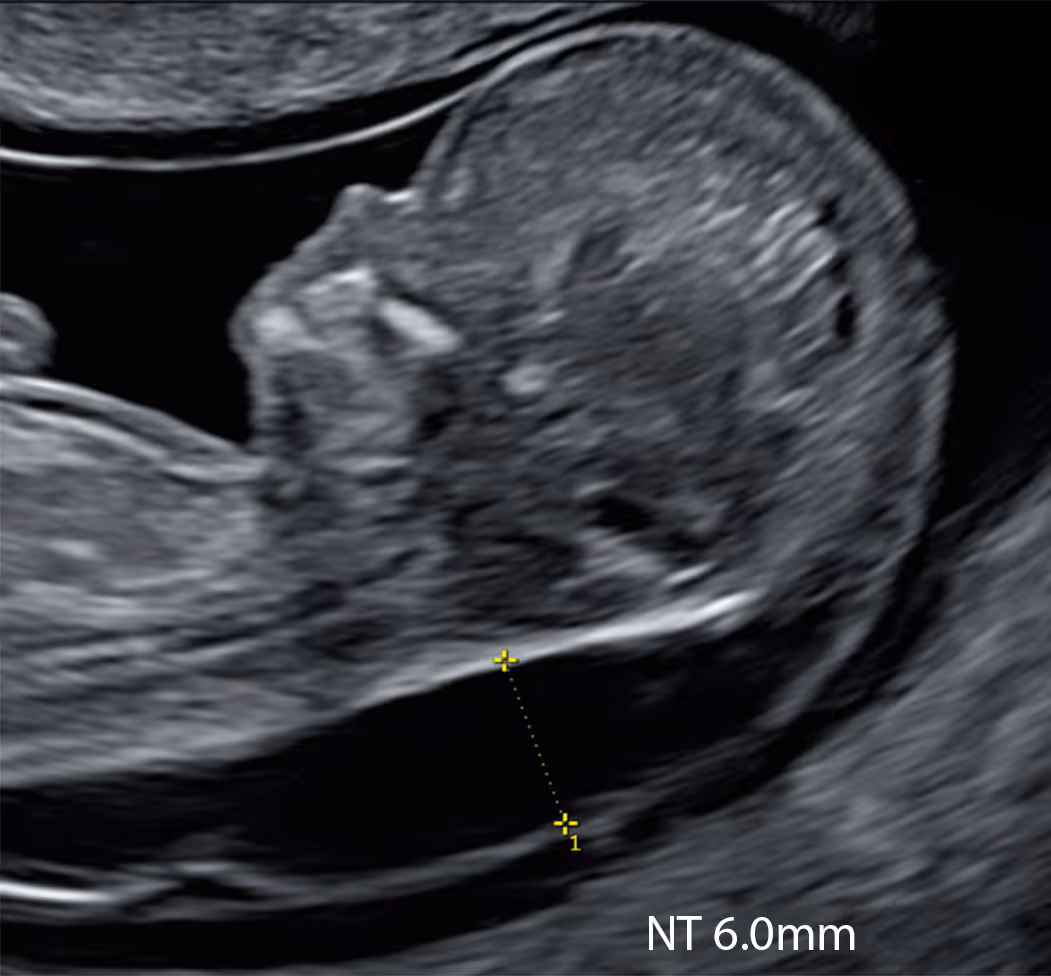

At the standard 11–14-week scan, increased nuchal translucency (NT) is most commonly defined as ≥ 3.5 mm. At 10 weeks (CRL < 45 mm), an NT of ≥ 2.5 mm is typically used as the cut-off

At 10 weeks (CRL under 45 mm), an NT of 2.5 mm or more is the most commonly used cut-off to define an abnormal increase.

At 10 weeks, abnormally increased NT (>2.5 mm) is uncommon, but when present it is a clinically significant finding.

An increased NT at 10 weeks is often a stronger sign of problems than the same finding later in pregnancy.

Midline Section: Full CRL view showing head and trunk in mid-sagittal section. The fetus may be face-up or back-up, as long as all mid-sagittal criteria are met.

Visualise: forehead and echogenic nasal tip, brainstem with typical “Z” shape, 4th ventricle and nuchal region

Skin line must be clearly seen, either separated from or merged with amnion. Spine must be straight.

Magnification: The fetal body should fill >60% of the screen.

Calliper Placement: Callipers should be placed on the inner borders of the nuchal translucency. Measurement must be perpendicular to the skin surface (crossbar orientation).